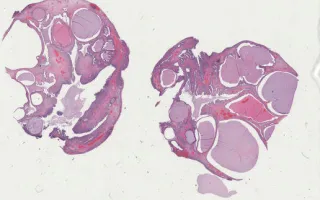

Cervix, High-grade squamous intraepithelial lesion, H&E stain

65 year old female with benign cytology on pap smear, presents with multiple cervical polyps.

High‐grade squamous intraepithelial lesions (HSILs) of the cervix are precursors of invasive cervical cancer (squamous cell carcinoma). The current HSIL classification corresponds to the older histological classification of CIN (cervical intraepithelial neoplasia) 2 or 3. In this case, HSIL is present incidentally within an endocervical polyp—an uncommon presentation.

Sections show an endocervical polyp with focal gland involvement by high grade squamous intraepithelial neoplasia (CIN 3). Involved areas show crowded squamous cells with enlarged, hyperchromatic and pleomorphic nuclei occupying the entire thickness of the epithelium. Mitoses are high and there is single-cell necrosis. Immunohistochemical staining shows strong, full thickness p16 reactivity and high Ki-67 proliferative index, further supporting the diagnosis of high grade cervical intraepithelial neoplasia.

This slide shows H&E stain. See related content for p16 stain.